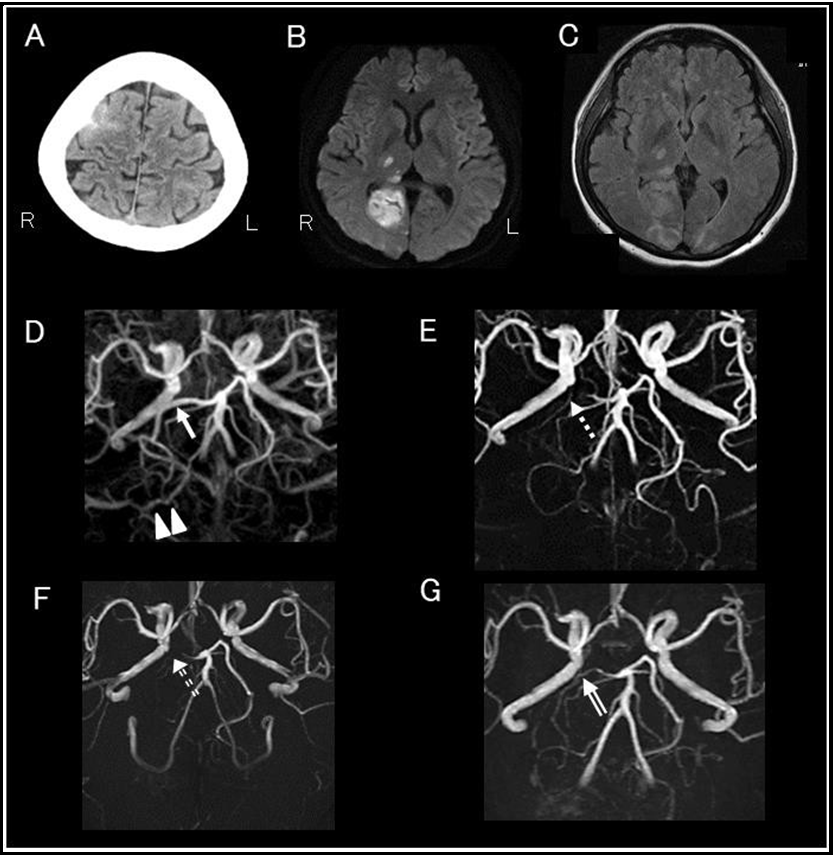

Improvement of intrapartum reversible cerebral vasoconstriction syndrome over 12 weeks after onset: A Case Report